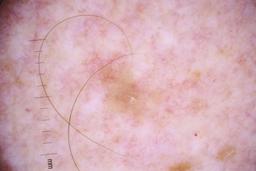

ISIC_4077341

Clinical

| Field | Value |

|---|---|

| acquisition_day | 1 |

| age_approx | 50 |

| anatom_site_1 | Trunk |

| anatom_site_2 | Anterior trunk |

| concomitant_biopsy | False |

| dermoscopic_type | contact non-polarized |

| diagnosis_1 | Benign |

| diagnosis_confirm_type | serial imaging showing no change |

| family_hx_mm | False |

| image_type | dermoscopic |

| lesion_id | IL_9238622 |

| patient_id | IP_1969685 |

| personal_hx_mm | True |

| sex | male |